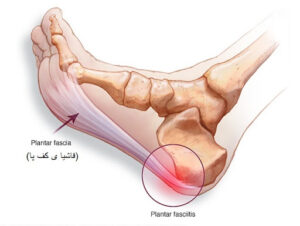

علائم مهم خار پاشنه در کودکان که نباید نادیده بگیرید + درمان

خار پاشنه در کودکان مشکلی است که میتواند باعث درد هنگام راه رفتن و بازی کردن شود. این مشکل معمولاً به دلیل فشار زیاد روی پاشنه یا کفش نامناسب ایجاد